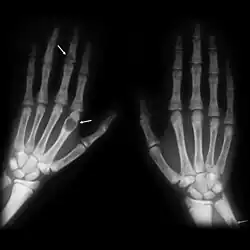

X-rays may also be used to diagnose the disease. Usually, these X-rays will show extremely thin bones, which are often bowed or fractured. However, such symptoms are also associated with other bone diseases, such as osteopenia or osteoporosis.[29] Generally, the first bones to show symptoms via X-ray are the fingers.[22] Furthermore, brown tumors, especially when manifested on facial bones, can be misdiagnosed as cancerous.[29] Radiographs distinctly show bone resorption and X-rays of the skull may depict an image often described as "ground glass" or "salt and pepper".[30][31] Dental X-rays may also be abnormal.[2]

The major symptoms of OFC are bone pain or tenderness, bone fractures, and skeletal deformities such as bowing of the bones. The underlying hyperparathyroidism may cause kidney stones, nausea, constipation, fatigue and weakness. X-rays may indicate thin bones, fractures, bowing, and cysts. Fractures are most commonly localized in the arms, legs, or spine.[2][3]

Generally, the first bones to be affected are the fingers, facial bones, ribs, and pelvis.[22][23] Long bones, which are longer than they are wide, are also among the first affected.[23] As the disease progresses, any bone may be affected.[18]